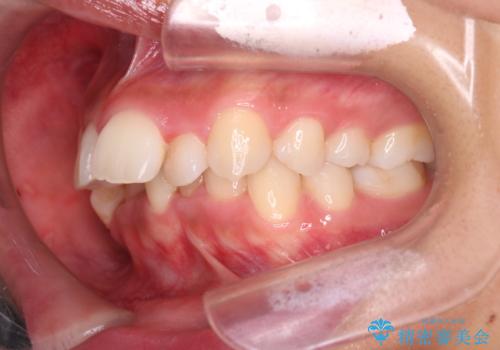

- 前歯の凸凹を主訴に来院されました。

抜歯を行い、ワイヤー矯正にて治療を行いました。

凸凹もなくなり、歯磨きもしやすくなったと喜んでいただきました。